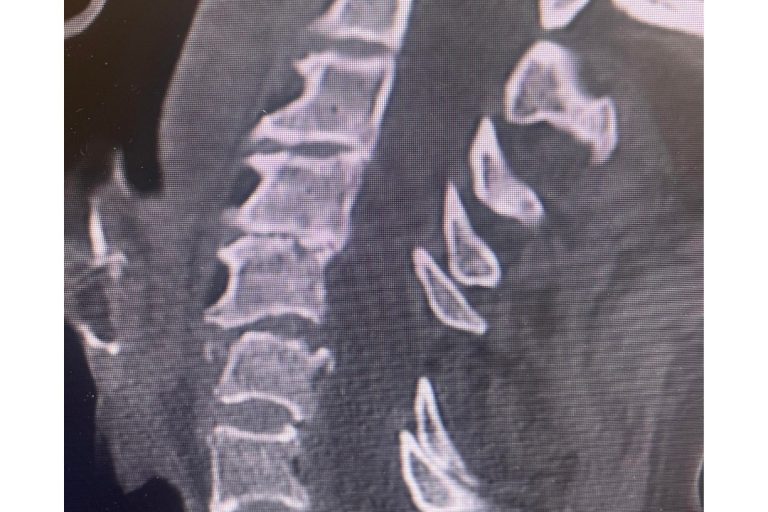

Meet Lin Sanders—a true inspiration of resilience and determination! Part 1 Lin underwent a complex two-level lumbar fusion at Texas Neuro-Spine Surgery. The procedure involved an anterior lumbar interbody fusion (ALIF) at L3-4 and L4-5, followed by laminectomies and pedicle screw instrumentation at the same levels. These surgeries were performed to help address her back…